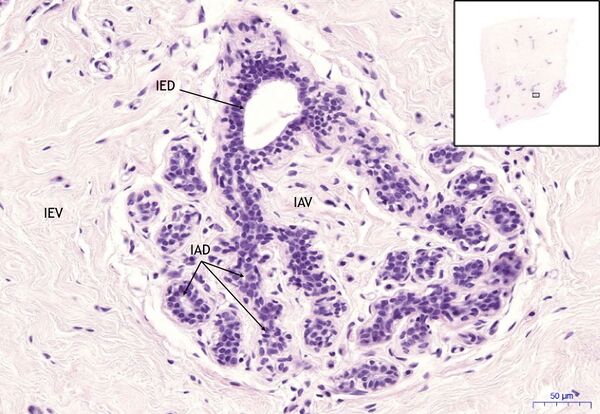

Mamma non lactans – HE 20x

Mamma non lactans:

- 1) L – lobule

- 2) IAD – intralobular duct

- 3) IAV – intralobular stroma

- 4) IED – interlobular duct

- 5) IEV – interlobular stroma

- 6) MEB – myoepithelial cells

- 7) F – fibroblast